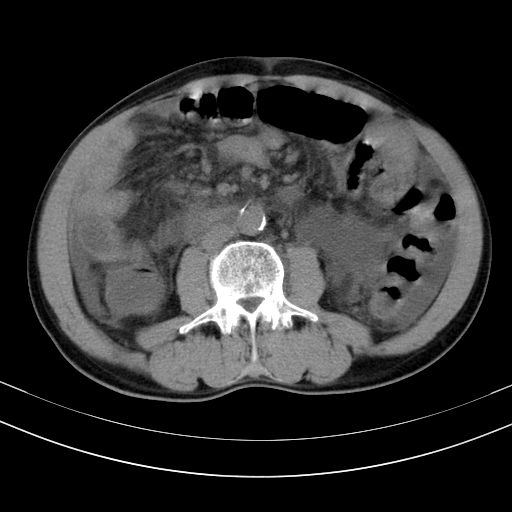

以下是引用随光逐影在2010-2-28 10:23:00的发言:[br]1)考虑肝癌;建议行ct增强扫描检查。2)肝硬化,脾大,腹水。3)慢性胆囊炎。

以下是引用dyqct在2010-2-28 16:44:00的发言:[br][quote]以下是引用随光逐影在2010-2-28 10:23:00的发言:[br]1)考虑肝癌;建议行ct增强扫描检查。2)肝硬化,脾大,腹水。3)慢性胆囊炎。